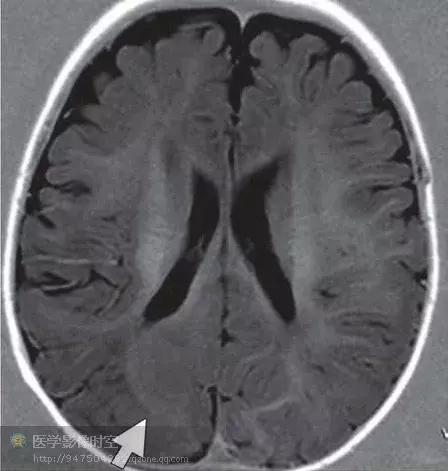

颞叶内侧硬化

颞叶内侧硬化是一种最常见的青少年癫痫病因。病理学上,特征是海马神经元丢失,胶质增生,也可以累及单侧穹窿和乳头体。临床上,病人常常具有皮质病变病史,例如颅内感染,外伤,或者5岁以前发生复杂性高热癫痫。初次治疗足以控制症状,部分病人实际上不需要治疗就可以痊愈。当癫痫复发的时候,常常为难治性。颞叶内侧硬化病人准确诊断受益最大,手术治疗具有90%的治愈率。

颞叶内侧硬化的诊断基于临床、脑电图和影像学检查。典型的磁共振成像特征包括T1WI上海马萎缩,T2WI上颞叶内侧高信号。然而,PET进行功能成像对海马硬化的敏感性更高,通常显示为高代谢区,大于海马范围。尤其是采用MR-PET融合图像时观察的效果更好。

图10a冠状T2WI显示右侧海马为T2高信号(箭)

图10b a稍后一点的冠状T2WI,右侧颞极白质(箭)与左侧正常脑白质(箭头)信号相比,呈现T2高信号。

图10c 冠状MR-PET融合图像显示右侧颞极低代谢活性。